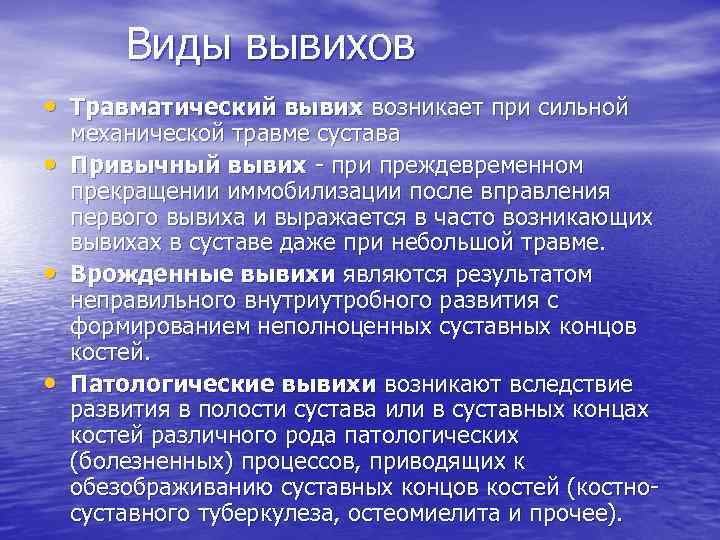

Виды вывихов • Травматический вывих возникает при сильной • • • механической травме сустава Привычный вывих - при преждевременном прекращении иммобилизации после вправления первого вывиха и выражается в часто возникающих вывихах в суставе даже при небольшой травме. Врожденные вывихи являются результатом неправильного внутриутробного развития с формированием неполноценных суставных концов костей. Патологические вывихи возникают вследствие развития в полости сустава или в суставных концах костей различного рода патологических (болезненных) процессов, приводящих к обезображиванию суставных концов костей (костносуставного туберкулеза, остеомиелита и прочее).

Виды вывихов • Травматический вывих возникает при сильной • • • механической травме сустава Привычный вывих - при преждевременном прекращении иммобилизации после вправления первого вывиха и выражается в часто возникающих вывихах в суставе даже при небольшой травме. Врожденные вывихи являются результатом неправильного внутриутробного развития с формированием неполноценных суставных концов костей. Патологические вывихи возникают вследствие развития в полости сустава или в суставных концах костей различного рода патологических (болезненных) процессов, приводящих к обезображиванию суставных концов костей (костносуставного туберкулеза, остеомиелита и прочее).